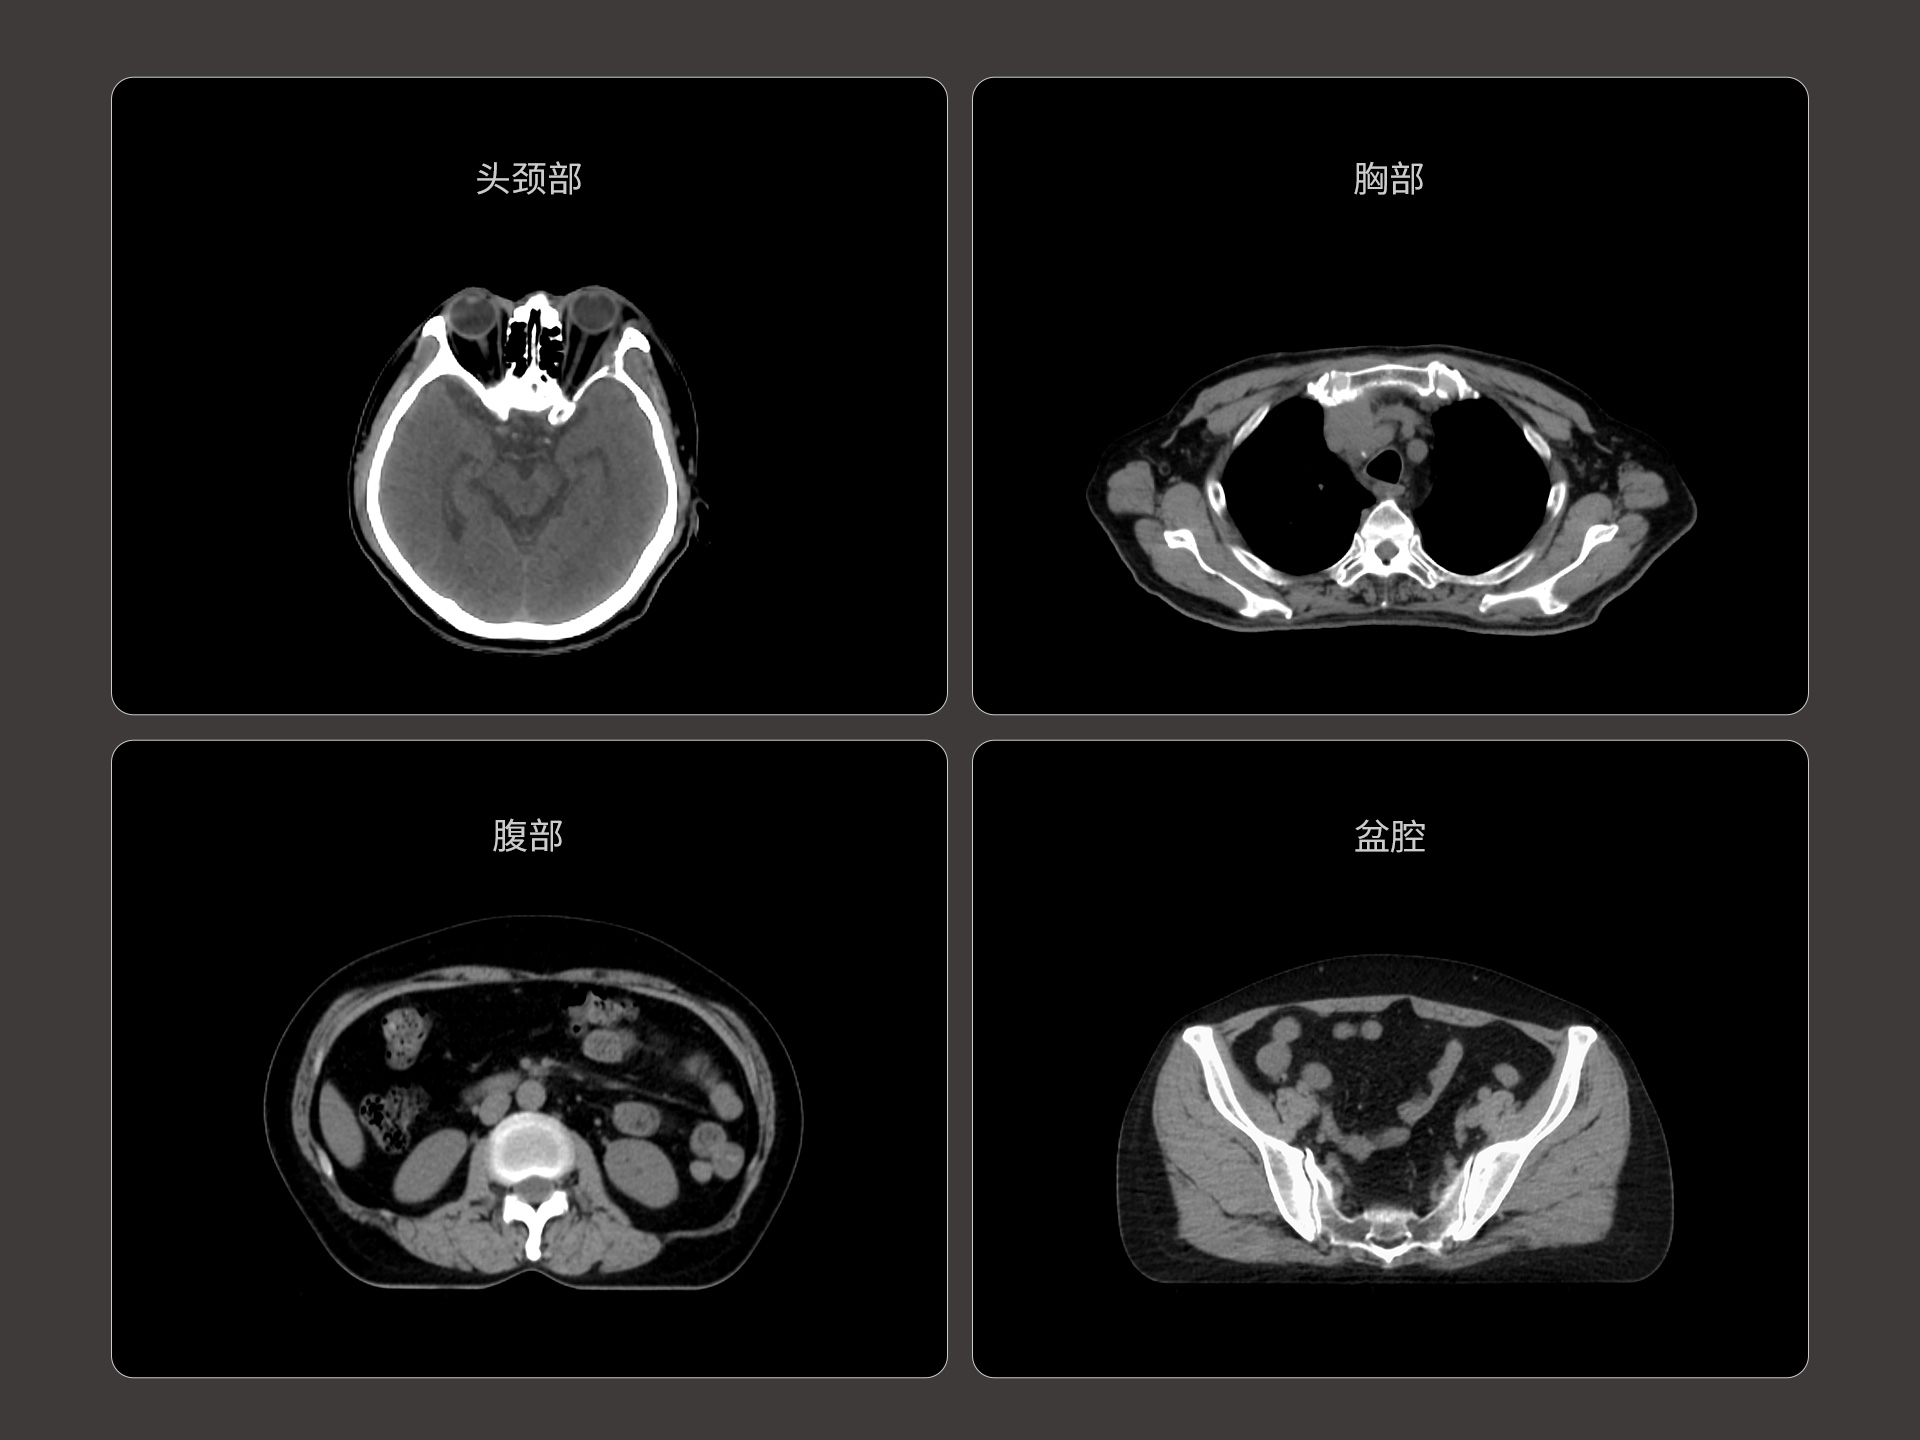

uLinac HalosTx®搭载新一代 87cm 大孔径诊断级CT图像引导系统,全能进阶,实现高清图像质量和全景视野的完美平衡,开辟全疗程 「影像感知」 ,为临床提供更自信、更全面的临床依据。

扇形束成像,极低散射,媲美CT-sim的影像品质

3mm @ 0.3% 高软组织对比度,0.55mm薄层扫描,精确鉴别肿瘤靶区边界

全疗程肿瘤变化感知,加速高清影像引导高水平普及

原生诊断级CT影像